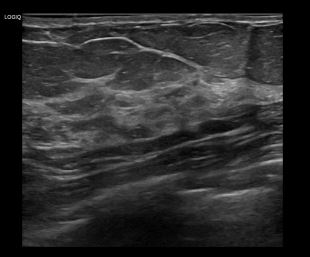

상기환자는 외부검사 이상소견으로 내원하신 60대 후반 여성분으로 의심스러운 좌측 혹 조직검사 시행해 유방암 진단되었습니다